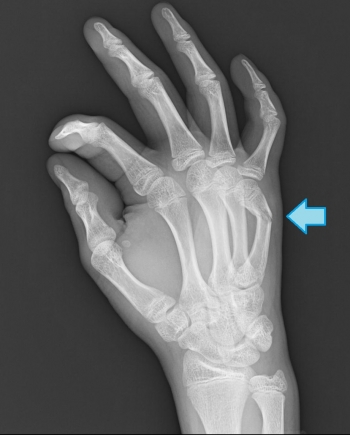

皆さん、突き指は一度はしたことがあると思いますが、そこには骨折もしている可能性があります。

早期にレントゲンを撮りましょうね